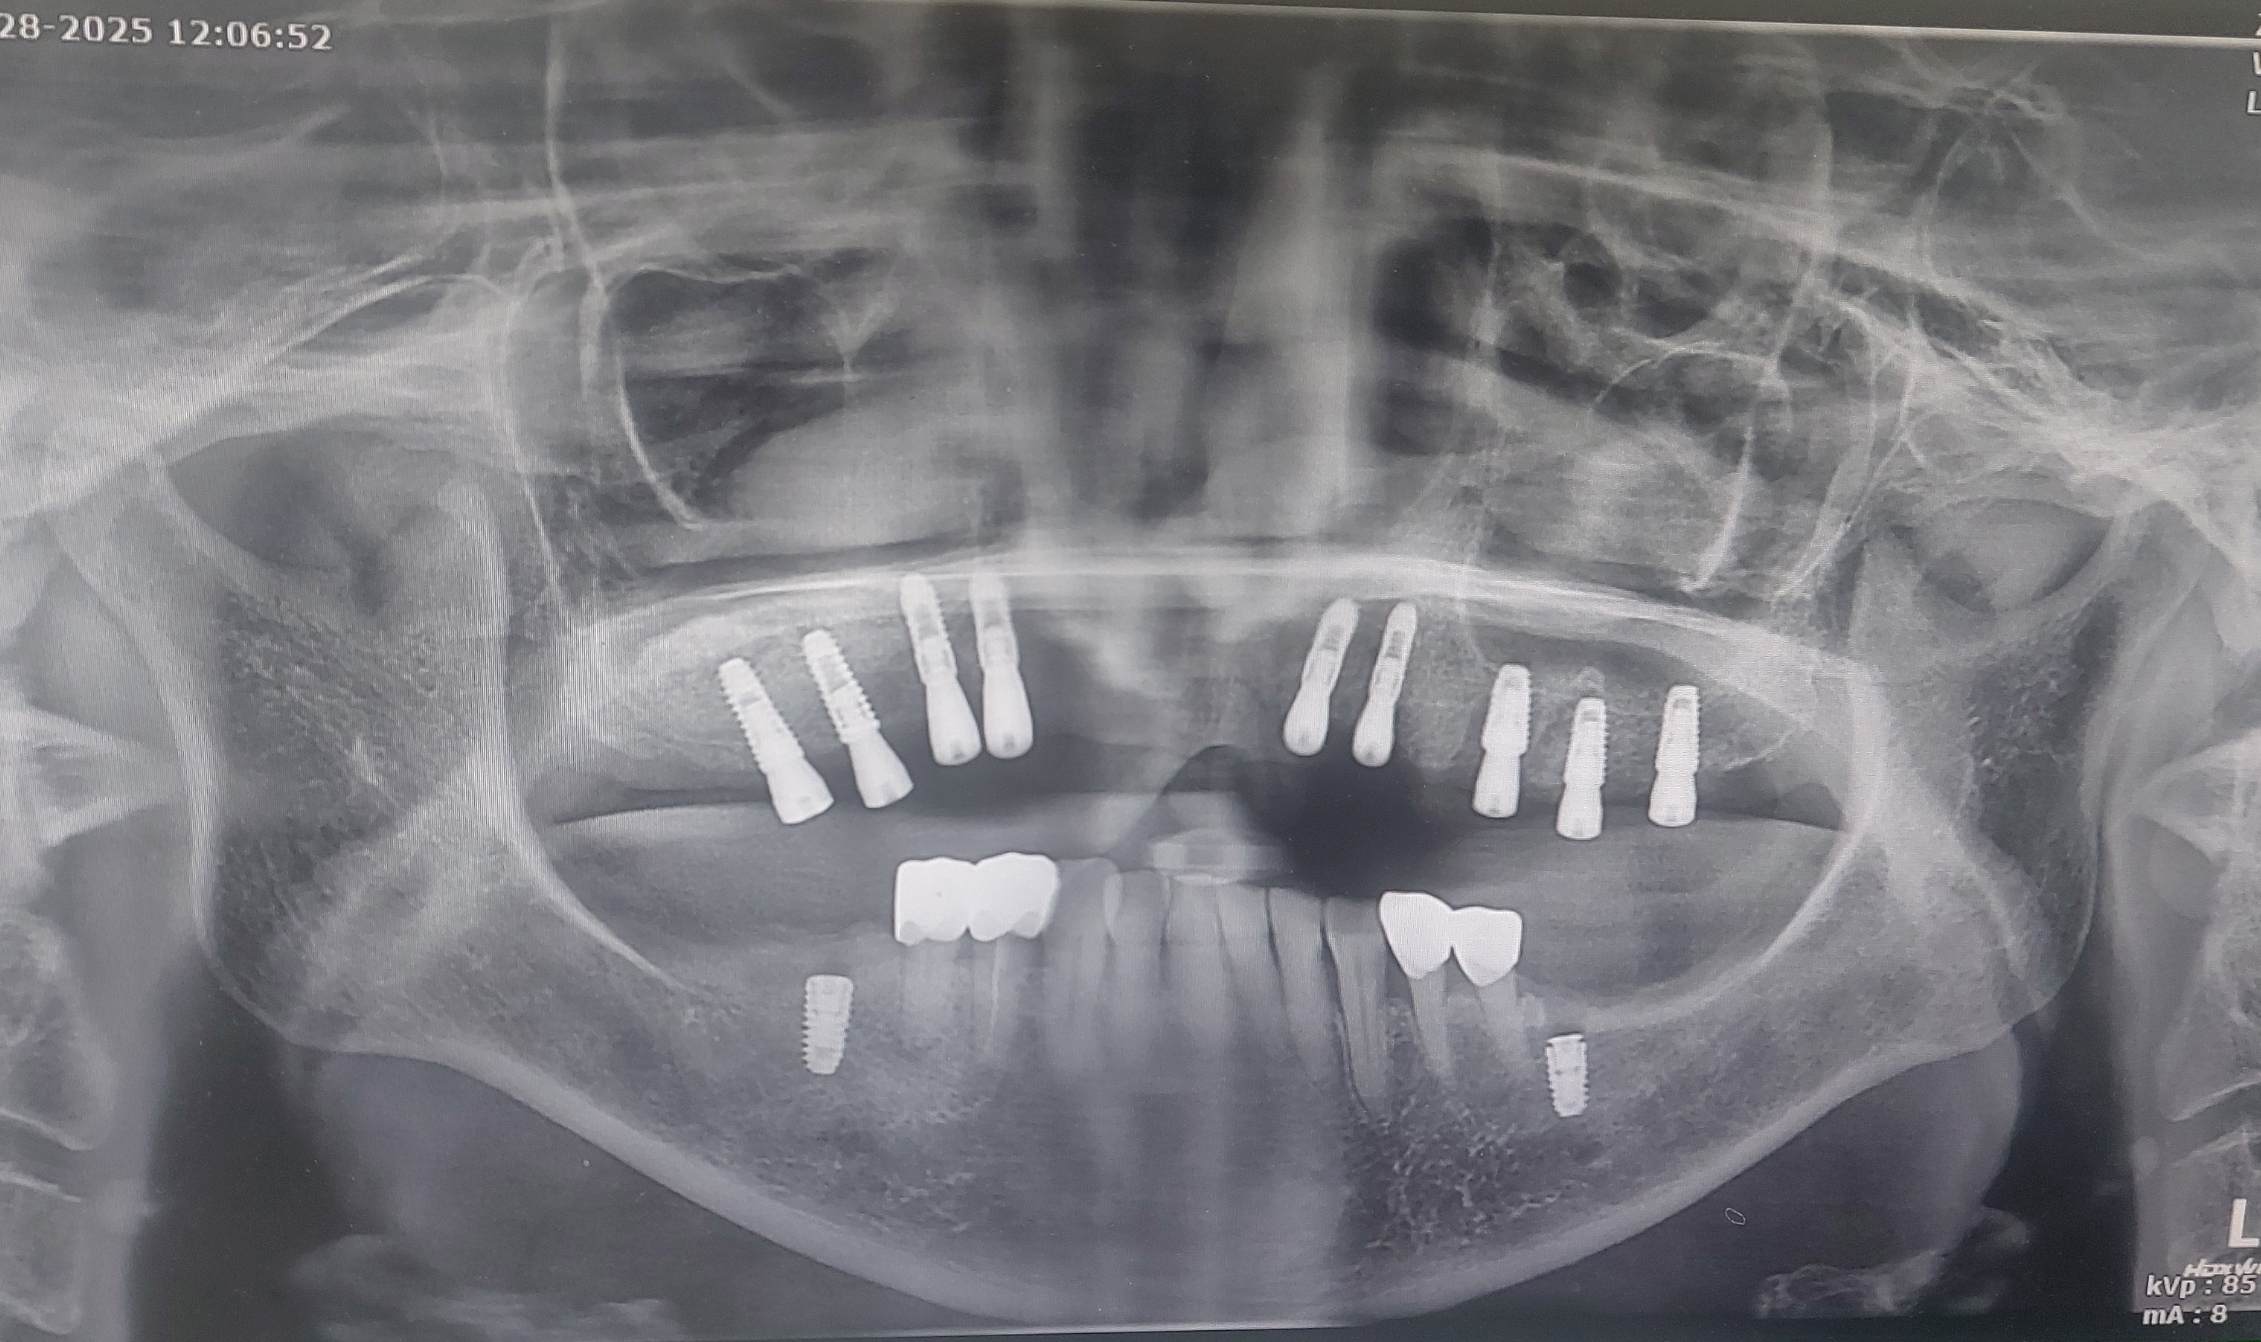

노란색으로 골이식이라고 적힌 부위는 광범위하게 상악동 거상술을 시행하여 골이식을 시행하였습니다.

*** 여기서 생각해 보아야 할 문제는 환자분의 골의 폭경이 좁은 편이었습니다.

구치부는 덴티움 임플란트 3.6 mm 를 식립하였고

전치부는 오스템의 3.5 mm 직경의 임플란트를 식립하였습니다.

사실 위 직경의 임플란트는 협소한 두께의 임플란트 이지만

우선 덴티움과 오스템 임플란트는 지대주가 미니 사이즈가 아니라 기존의 regular implant의 직경과 동일한 지대주의 굵기를 사용할 수 있어서 추후 보철물의 안정성에 많은 도움이 됩니다.

(타사의 제품들들 직경이 좁은 임플란트의 경우 지대주도 같이 너무 얇아지는 경향이 있지만 오스템 제품은 그 두께가 어느 정도 유지 되기에 저는 특히 전치부의 직경이 얇은 곳은 오스템 임플란트를 이용하여 수술을 진행하고 있습니다.)

임플란트 식립후 약 5개월뒤 이차수술을 시행하는 날 하악에 임플란트를 식립하였습니다.

이는 위 전체 일차 수술과 이번에 시행한 이차수술 모두 수면마취로 진행하였기에 아래도 같이 식립해 드렸습니다.